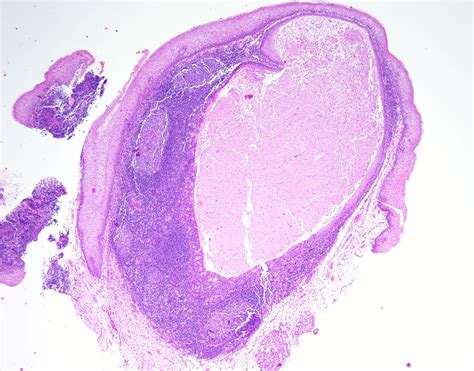

A Mucus Retention Cyst—frequently referred to as a mucocele when found in the mouth—is essentially a small sac filled with mucus. These cysts develop when the duct of a salivary gland or a mucus-producing gland in the sinus lining becomes obstructed or damaged. When this happens, the mucus has nowhere to go, leading to a localized swelling.

The nature of these cysts varies depending on their location. In the mouth, they appear as painless, soft, bluish or translucent bumps, commonly found on the lower lip, the underside of the tongue, or the floor of the mouth. Conversely, when they occur in the maxillary sinuses, they are often discovered incidentally during routine dental X-rays or sinus imaging, as they rarely cause symptoms unless they grow large enough to obstruct the sinus cavity.

• Biopsy: In rare cases where the diagnosis is uncertain, a small sample of the tissue may be removed for microscopic examination.